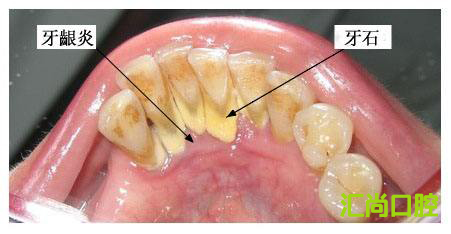

牙結(jié)石是怎么形成的,又有什么危害

現(xiàn)在基本上所有的人都有愛刷牙的好習(xí)慣,那么為什么每天都在刷牙還會(huì)有牙結(jié)石呢?這時(shí),我們就需要了解一下牙結(jié)石是怎么形成的。

首先,我們經(jīng)常見到牙縫里面的紅色物質(zhì),這種物質(zhì)被稱作牙菌斑,牙菌斑是粘附在牙齒表面的,不易被沖走,這就給更多的細(xì)菌提供肥沃的土壤,而且一般會(huì)在兩小時(shí)左右迅速增厚,所以我們應(yīng)當(dāng)在12小時(shí)左右清除牙菌斑。

然后,如果清除不及時(shí),細(xì)菌就會(huì)大量繁殖,如果再不注意口腔衛(wèi)生,牙菌斑和食物殘?jiān)鼤?huì)在唾液的浸泡下經(jīng)過24小時(shí)被唾液中的成分鈣化,這就形成了初期的牙結(jié)石。隨著時(shí)間的推移,牙結(jié)石會(huì)繼續(xù)沉積,越積越多,越積越硬,到后期刷牙是去不掉的,只能通過洗牙去解決。

那么牙結(jié)石又有什么危害呢?匯尚口腔的醫(yī)生總結(jié)出了三個(gè):

第一:導(dǎo)致口臭。牙齒中有異物,一般都會(huì)有口臭,但是可能自己聞不到,身邊的人就要遭殃了。

第二:導(dǎo)致牙齦疾病。牙結(jié)石如果長(zhǎng)期不處理,會(huì)引起牙齦組織的水腫、充血、糜爛等情況,如果繼續(xù)發(fā)展,可造成牙周組織溢膿,甚至牙齒松動(dòng)。如果是孩子,一定要防止牙結(jié)石的形成,否則成年后就可能成為牙周病患者的一員。

第三:導(dǎo)致牙齒松動(dòng)。牙結(jié)石從牙冠逐漸向下蔓延,牙結(jié)石每進(jìn)步一些,牙槽骨就萎縮一些。久而久之,牙齒就逐漸松動(dòng),這時(shí)牙結(jié)石便見縫插針,逐漸蔓延到牙根部位,嚴(yán)重的會(huì)導(dǎo)致牙齒脫落。

從上我們可以看出,牙結(jié)石對(duì)牙齒的危害還是非常大的,為了牙齒健康,大家一定要養(yǎng)成定期洗牙的習(xí)慣,上海匯尚口腔專業(yè)洗牙、拔牙、種植牙等牙齒項(xiàng)目,咨詢電話:021-52981020